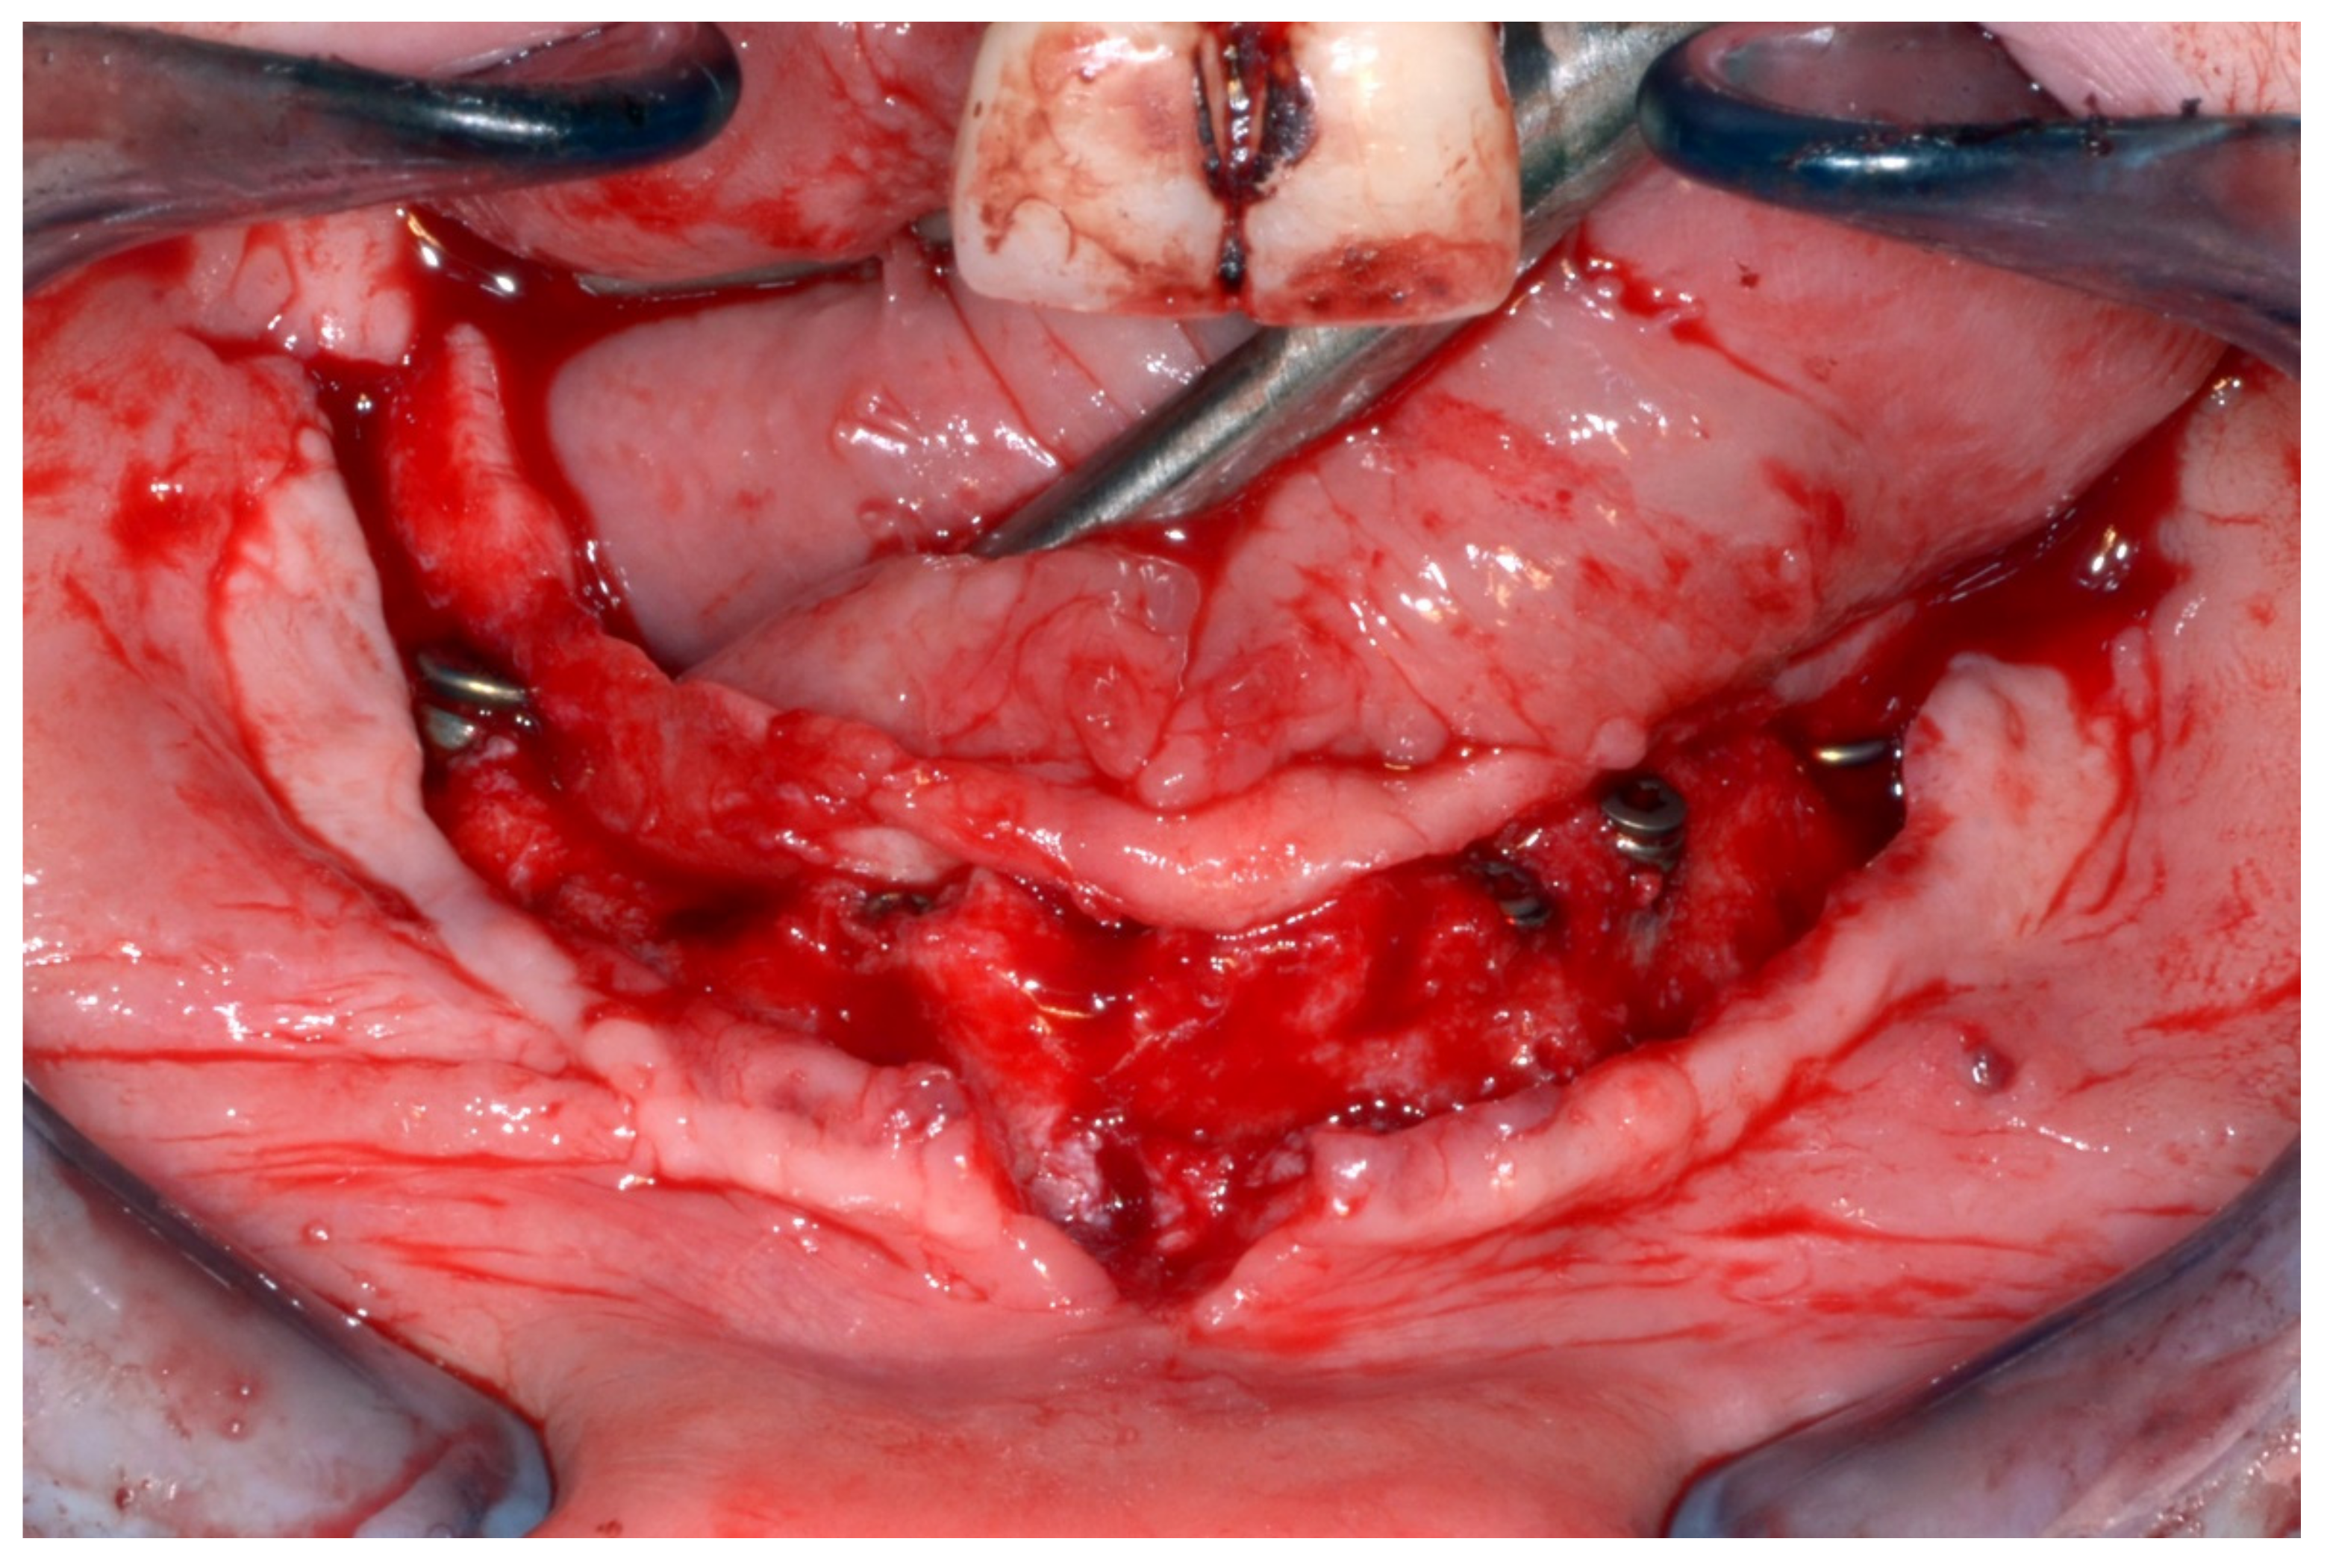

6.2.4. Intra-Operative Documentation:

In March 2013, twelve guided dental implants were placed at sites # 12, # 13, # 15, # 22, # 23, # 25, # 33, # 34, # 36, # 43, # 44, and # 46 (Figure 22, Figure 23, Figure 24, Figure 25 and Figure 26)

Mandibular surgical drilling guides temporarily supported and fixed with mini-screws.

Implant bed preparation using guided drills inserted into specific ad hoc drill handles.

Guided implant insertion.

Mandibular implants in place.